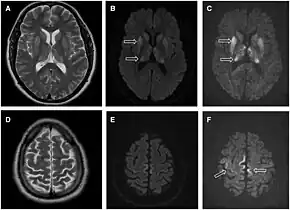

- MRI with diffusion weighted inversion (DWI) and fluid-attenuated inversion recovery (FLAIR) shows a high signal intensity in certain parts of the cortex (a cortical ribboning appearance), the basal ganglia, and the thalami.[36] The most common presenting patterns are simultaneous involvement of the cortex and striatum (60% of cases), cortical involvement without the striatum (30%), thalamus (21%), cerebellum (8%) and striatum without cortical involvement (7%). In populations with a rapidly progressive dementia (early in the disease process), MRI has a sensitivity of 91% and specificity of 97% for diagnosing CJD.[43] The MRI changes characteristic of CJD may also be seen in the immediate aftermath (hours after the event) of autoimmune encephalitis or focal seizures.[36]

Brain MRI is the most useful imaging modality for changes related to CJD. Of the MRI sequences, diffuse-weighted imaging sequences are most sensitive.[49] Characteristic findings are as follows:

- Focal or diffuse diffusion-restriction involving the cerebral cortex and/or basal ganglia. The most characteristic and striking cortical abnormality has been called "cortical ribboning" or "cortical ribbon sign" due to hyperintensities resembling ribbons appearing in the cortex on MRI.[50] The involvement of the thalamus can be found in sCJD, is even stronger and constant in vCJD.[51]

- Varying degree of symmetric T2 hyperintense signal changes in the basal ganglia (i.e., caudate and putamen), and to a lesser extent globus pallidus and occipital cortex.[47]

- ↑ Fragoso DC, Gonçalves Filho AL, Pacheco FT, Barros BR, Aguiar Littig I, Nunes RH, Maia Júnior AC, da Rocha AJ (2017-01-01). "Imaging of Creutzfeldt–Jakob Disease: Imaging Patterns and Their Differential Diagnosis". Radiographics. 37 (1): 234–257. doi:10.1148/rg.2017160075. PMID 28076012.

- 1 2 Finkenstaedt M, Szudra A, Zerr I, Poser S, Hise JH, Stoebner JM, Weber T (June 1996). "MR imaging of Creutzfeldt–Jakob disease". Radiology. 199 (3): 793–8. doi:10.1148/radiology.199.3.8638007. PMID 8638007.

- ↑ Ukisu R, Kushihashi T, Kitanosono T, Fujisawa H, Takenaka H, Ohgiya Y, Gokan T, Munechika H (February 2005). "Serial diffusion-weighted MRI of Creutzfeldt–Jakob disease". AJR. American Journal of Roentgenology. 184 (2): 560–6. doi:10.2214/ajr.184.2.01840560. PMID 15671380.

- ↑ Kumaran SP, Gupta K, Pushpa BT, Viswamitra S, Joshy EV (2012). "Diffusion-weighted imaging: As the first diagnostic clue to Creutzfeldt Jacob [sic] disease". Journal of Neurosciences in Rural Practice. 3 (3): 408–410. doi:10.4103/0976-3147.102645. ISSN 0976-3147. PMC 3505356. PMID 23189017.

- ↑ Abdulmassih R, Min Z (March 2016). "An ominous radiographic feature: cortical ribbon sign". Internal and Emergency Medicine. 11 (2): 281–3. doi:10.1007/s11739-015-1287-4. PMID 26238299.

- ↑ Tschampa HJ, Mürtz P, Flacke S, Paus S, Schild HH, Urbach H (May 2003). "Thalamic involvement in sporadic Creutzfeldt–Jakob disease: a diffusion-weighted MR imaging study". AJNR. American Journal of Neuroradiology. 24 (5): 908–15. PMC 7975779. PMID 12748093. Archived from the original on 10 October 2008.